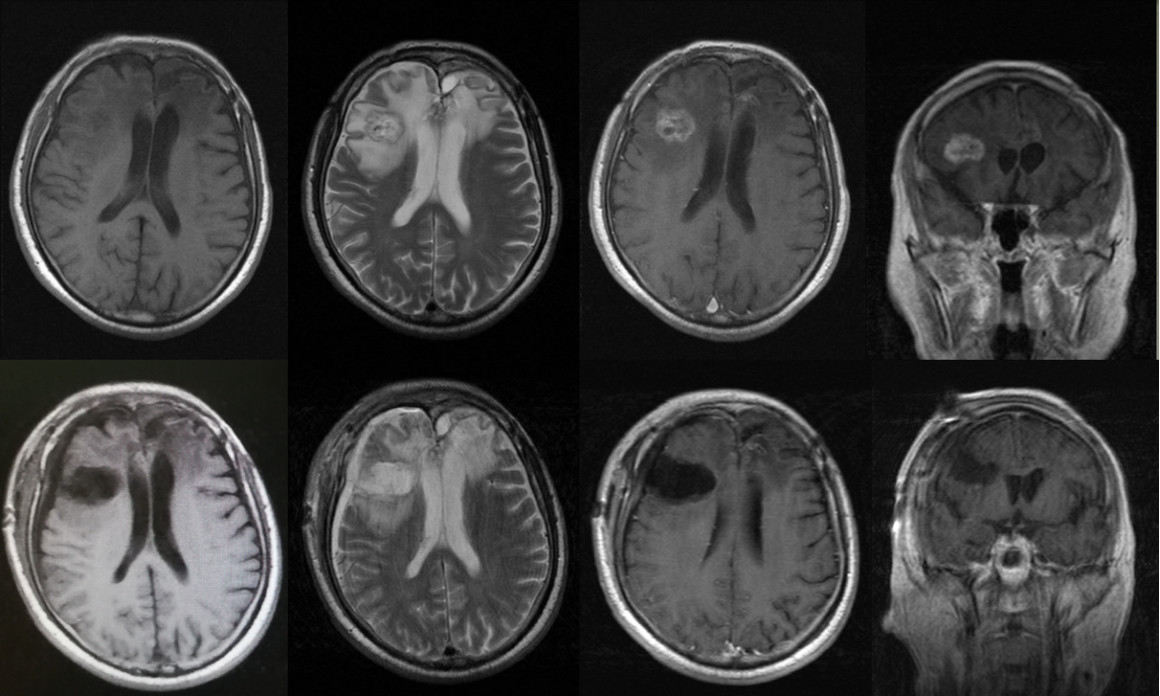

术后早期患者症状无加重,仍表现为淡漠和轻微言语混乱;术后3月淡漠及言语混乱基本恢复正常,轻微性格改变。术后MRI提示肿瘤全切,术后病理提示为胶质母细胞瘤(图3)。

图3. 术后早期CT及MRI复查提示肿瘤全切,病理提示为胶质母细胞瘤。

术后患者接受了标准剂量的放疗和替莫唑胺化疗。术后2年常规复查发现右额新发病灶,考虑肿瘤复发,随再次入院手术切除复发病灶,病理证实为复发胶质母细胞瘤,术后患者恢复良好,再次接受了标准剂量的替莫唑胺化疗。目前患者已随访3年,一般情况良好(图4)。

图4. 术后2年右侧额叶新发一病灶,手术病理证实为胶质母细胞瘤复发。